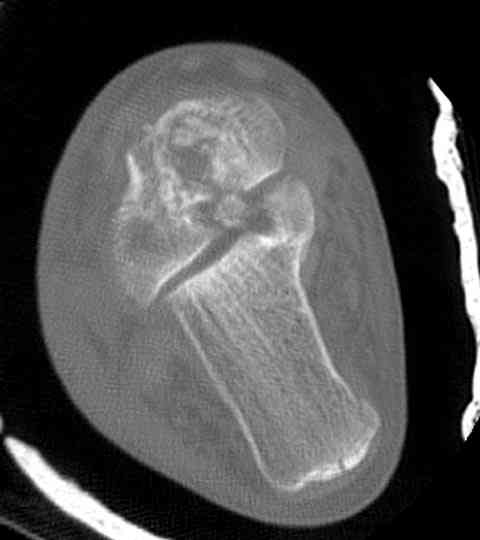

На ренгенограмме не уловил многоскольчатость тарана, чтобы доказать, конечно, можно было исследовать на КТ, потом КТ дает ориентацию фрагментов.

Два фрагмента суставной поверхности тарана можно восстановить боковой компрессией шурупами и дополнительно костная пластика.

(кстати, на нашем случае была применена костная пластика-allograft crouton для заполнения дефектов)